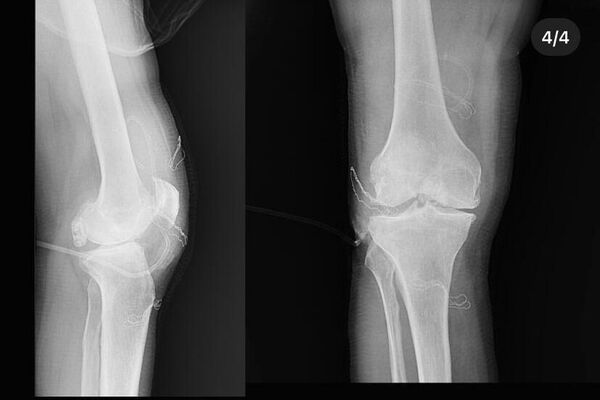

DÜ Tıp Fakültesi Hastanesinde endoskopik yöntemle gerçekleştirilen ameliyatla hastanın dizinden söz konusu parçalar çıkarıldı.

Doç. Dr. Zekeriya Okan Karaduman, Doç. Dr. Mehmet Arıcan ve Dr. Öğr. Üyesi Sönmez Sağlam tarafından çıkarılan parçaların boyutlarının birkaç milimetre ile santimetre arasında değiştiği belirtildi.

Eklem faresinin tespiti Röntgen kullanılarak kolay bir şekilde yapılabilir. Ciddi boyutlarda olan serbest cisimlere cerrahi tedavi uygulanır ve parçacık bulunduğu bölgeden direk alınır. Cerrahi tedavi sonrası kişilerin fizik tedavi süreci başlar. Şişlik, ağrı ve kas zayıflığı, kas kısalığı gibi durumlarda dokuyu eski haline getirerek tedavi süreci tamamlanmış olur.